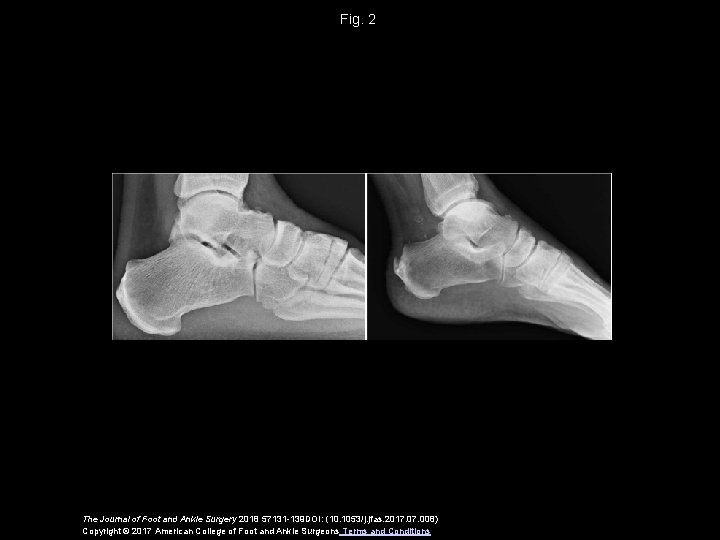

Fig. 2 The Journal of Foot and Ankle Surgery 2018 57131 -139 DOI: (10. 1053/j. jfas. 2017. 008) Copyright © 2017 American College of Foot and Ankle Surgeons Terms and Conditions